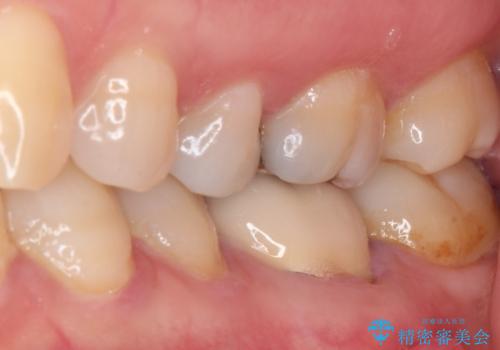

- 上下の奥歯に違和感を感じ、近医にて虫歯を指摘されたとのことで来院された患者様です。

診査したところ、下顎の奥歯は膿の出口ができており、上顎の奥歯は噛んだときに痛みを感じている状態でした。

まずは根管治療を行い、症状が落ち着いたことを確認して、オールセラミッククラウンにて補綴治療を行うこととしました。